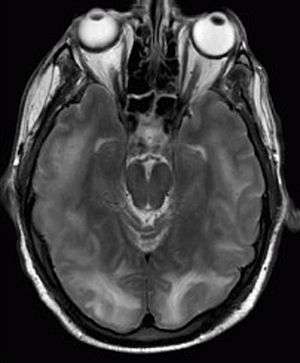

| Posterior reversible encephalopathy syndrome visible on magnetic resonance imaging as multiple cortico-subcortical areas of T2-weighted hyperintense (white) signal involving the occipital and parietal lobes bilaterally and pons. | |

Posterior reversible encephalopathy syndrome (PRES), also known as reversible posterior leukoencephalopathy syndrome (RPLS), is a syndrome characterized by headache, confusion, seizures and visual loss. It may occur due to a number of causes, predominantly malignant hypertension, eclampsia and some medical treatments. On magnetic resonance imaging (MRI) of the brain, areas of edema (swelling) are seen. The symptoms tend to resolve after a period of time, although visual changes sometimes remain.[1][2] It was first described in 1996.[3]

The diagnosis is typically made clinically, with supportive findings on magnetic resonance imaging of the brain; this may show hyperintensities on T2-weighed imaging. Three different patterns have been described on MRI imaging including: superior frontal sulcus pattern, dominant parieto-occipital pattern, and holohemispheric watershed pattern.[5][7]